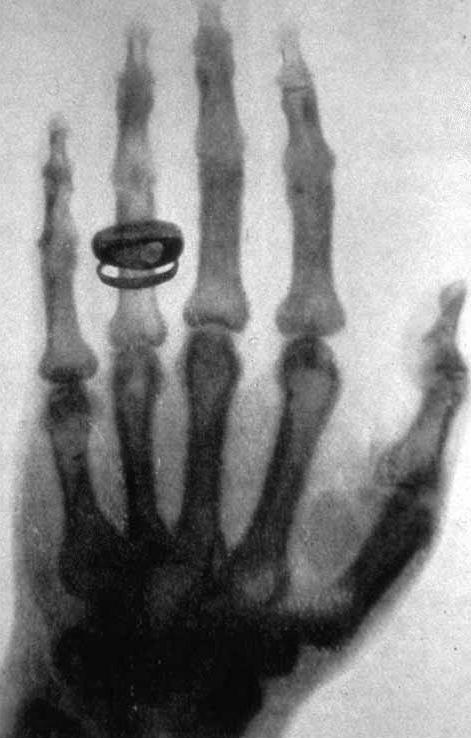

Pocos días después, Röntgen tomó una de las imágenes más icónicas de la historia de la ciencia: la radiografía de la mano de su esposa, Anna Bertha Ludwig, donde se veían con nitidez sus huesos y el anillo de bodas. La fotografía causó asombro en el mundo académico y marcó el inicio de una nueva disciplina: la radiología. Por primera vez, el ser humano podía observar el interior del cuerpo sin recurrir a la cirugía.